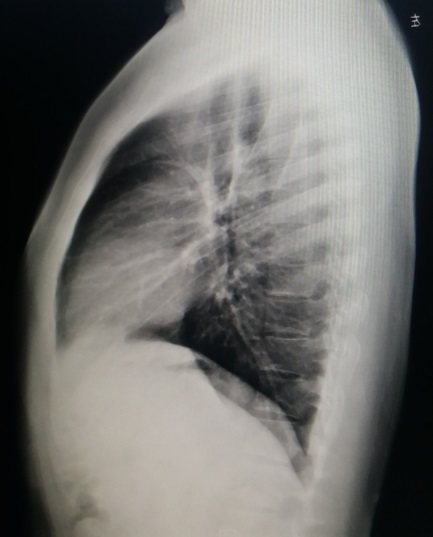

患者入院后,体检发现,其身体较为肥胖,胸廓整体外观为桶状,体表脂肪较多,但前胸壁骨性结构明显前突(图1,2,3)。X线检查,正位片提示肋间隙宽度正常,肺野肺纹理正常,无肺气肿征象(图4),侧位片提示前胸壁整体前突(图5)。行CT检查,胸廓整体呈现桶状,胸壁前后径增加,截面外观接近圆形,肺野无异常(图6)。胸廓顶部桶状不明显(图7),但从心底部水平开始(图8),前胸壁前突逐渐加重,一直延续到肋弓水平(图9,10)。三维重建显示桶状外观(图11,12)。

图5,X线侧位片提示桶状胸。